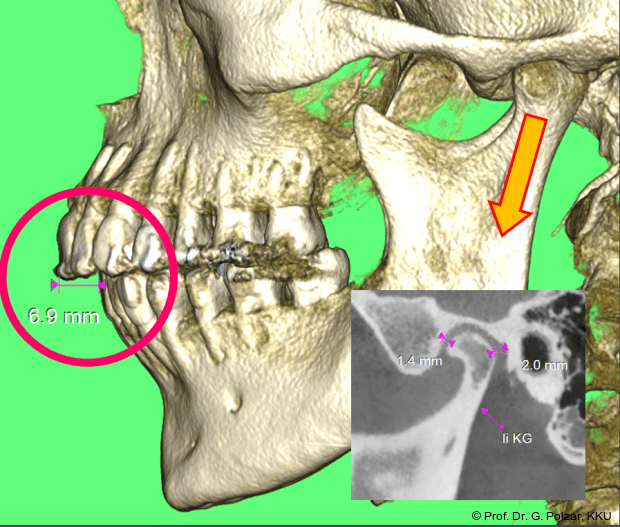

KG-Position: Die 3D-Ansicht im DVT zeigt eine vorverlagerte UK-Position bei neutraler Okklusion (Abb. 4a+b).

Im Sagittalschnitt zeigen beide Kiefergelenke eine deutlich anteriore Position. Der dorsokraniale Abstand betrug rechts 7,0 mm und links 5,8 mm. In der PEP waren sie im lateralen Bereich ca. 1 mm kleiner als in der Mitte der Sagittalprojektion (Abb. 6a–d).

Diese deutlich anteriore Gelenkposition im Neutralbiss ließ den Verdacht auf einen Sunday Bite zu. Das heißt, die Patientin schob den Unterkiefer aktiv nach vorne, um damit schönere Schneidezahnkontakte bzw. eine vermeintlich neutrale Okklusion zu erreichen. Nach mühsamen Lockerungsübungen gelang es der Patientin, auch in die zen­trale Kiefergelenkposition zu wechseln. So zeigte sich das ganze Ausmaß der Malokklusion. In neutraler KG-Position hatte die Patientin eine sagittale Frontzahnstufe von ca. 7 mm mit 1 PB Klasse II-Okklusion im Seitenzahn­bereich (Abb.5a+b, 7a–c).